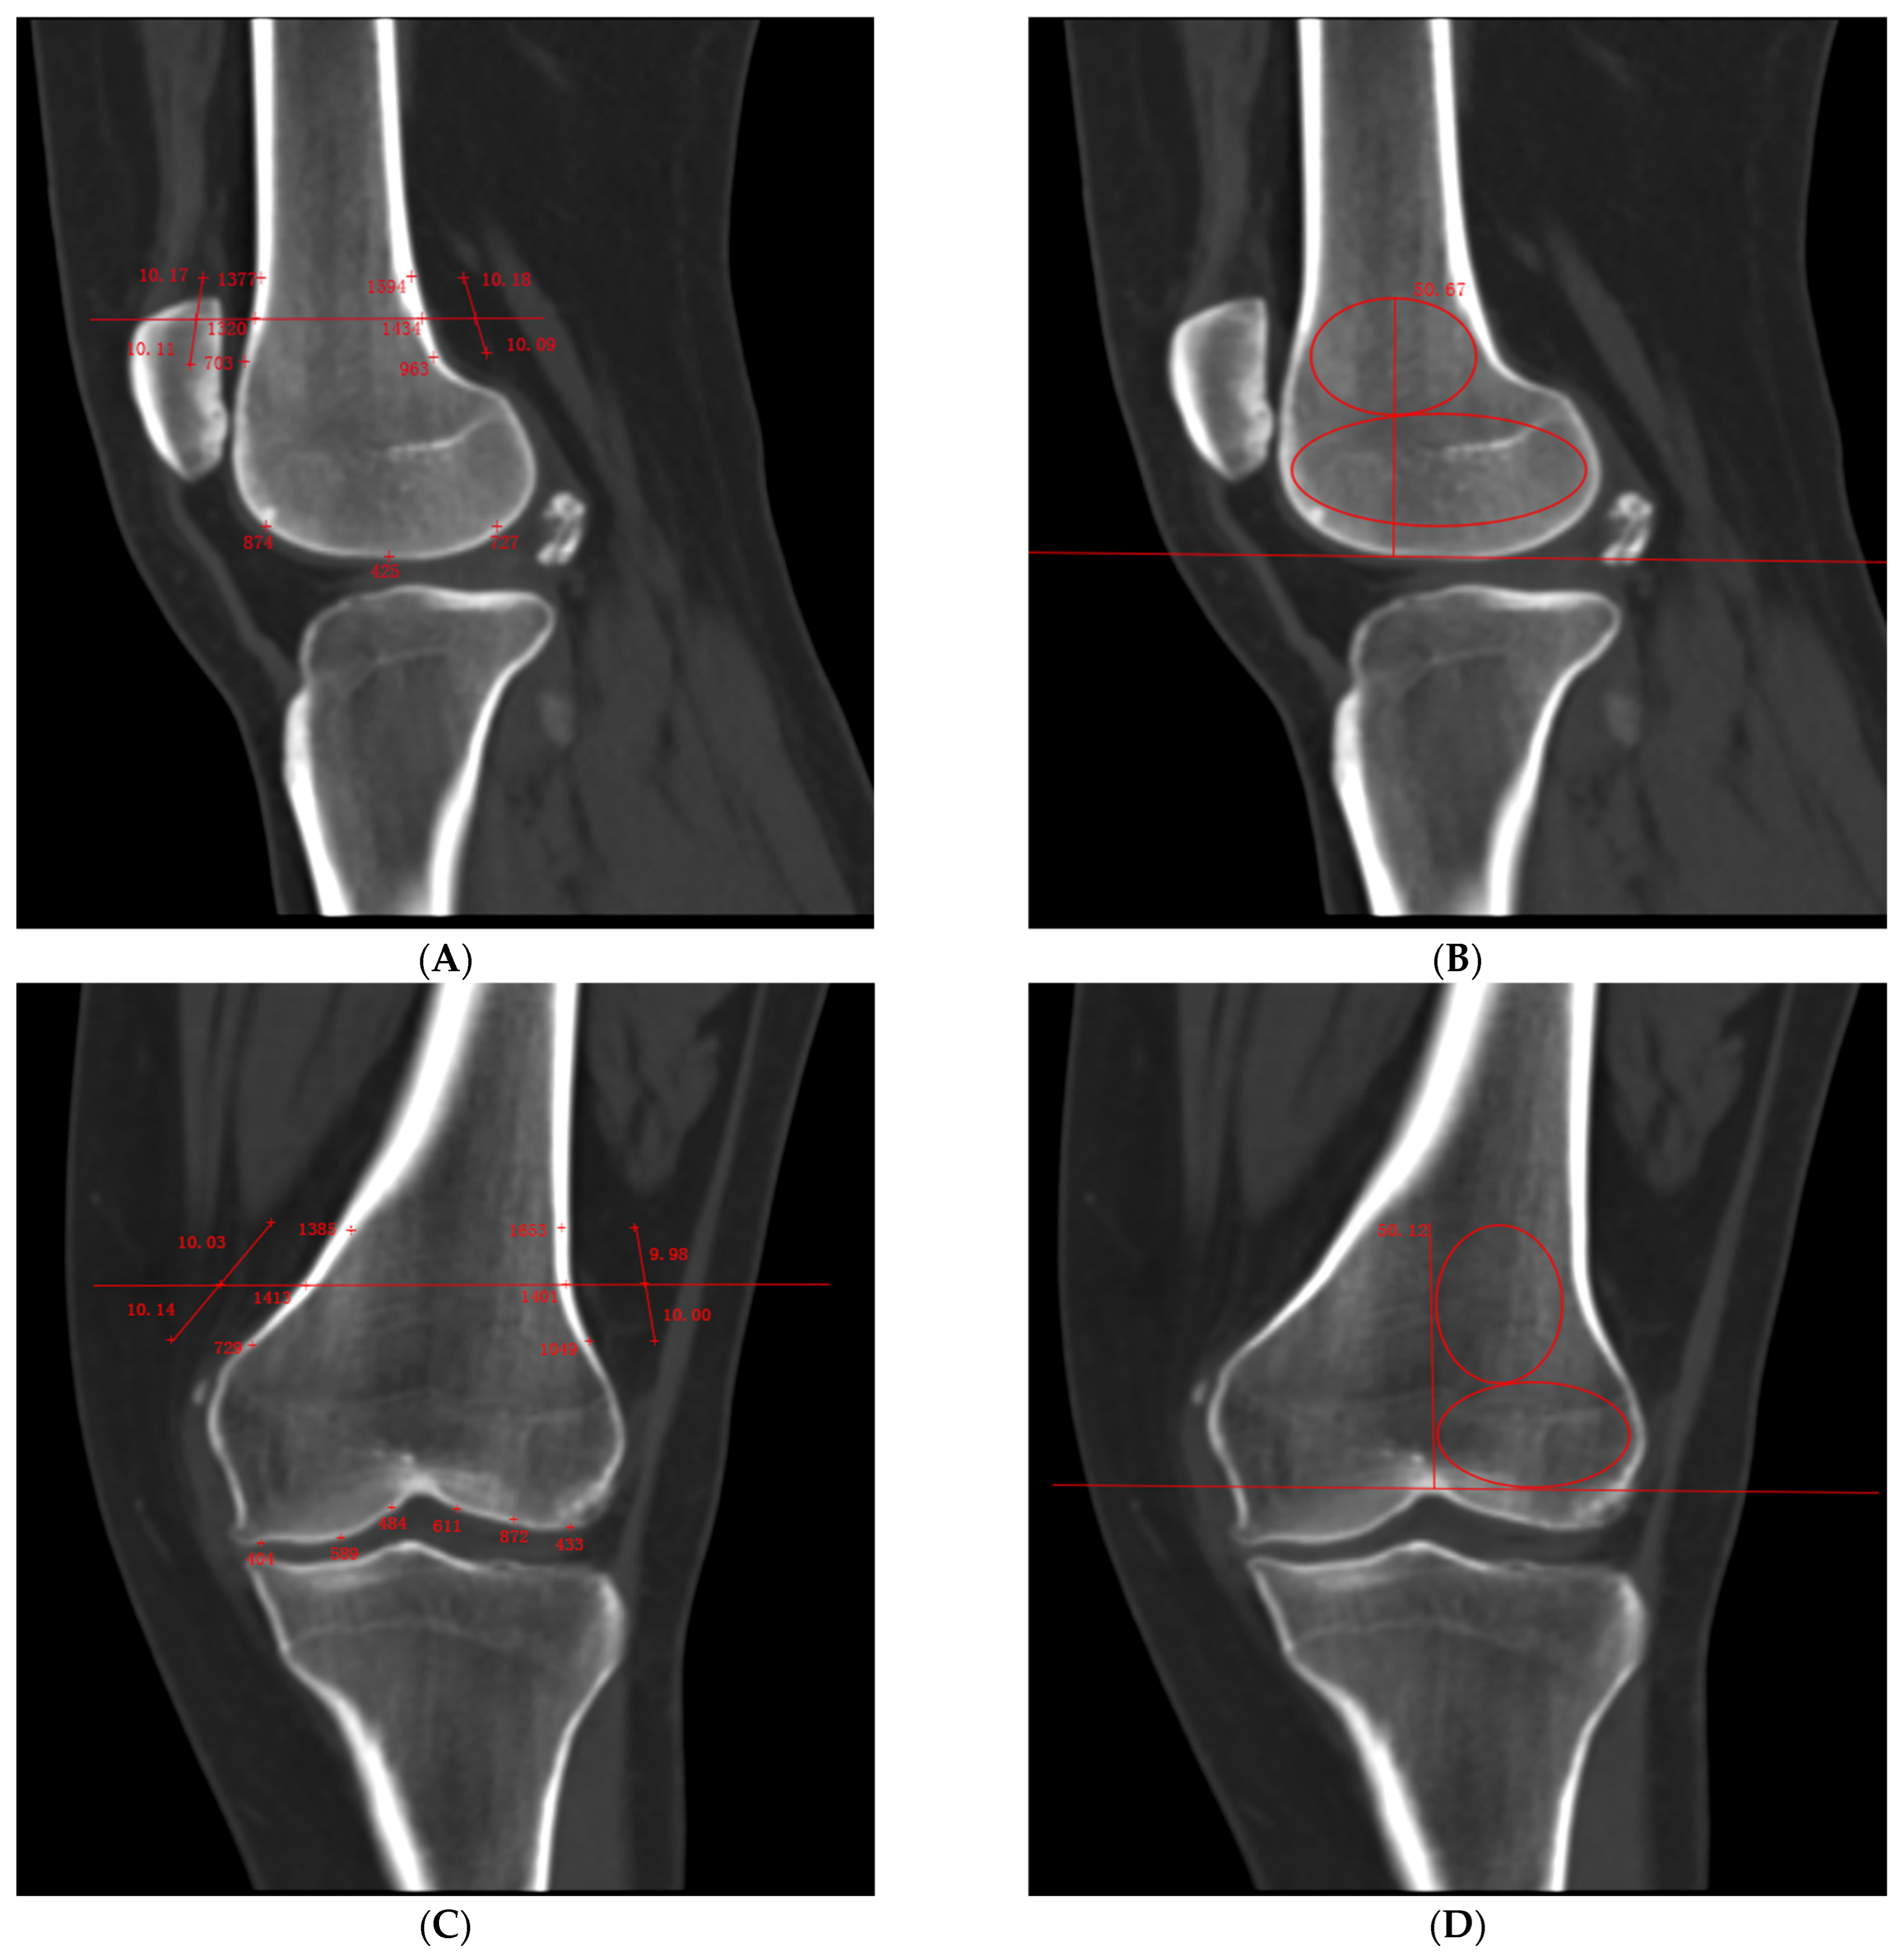

裁断済 Diagnostic Imaging: Musculoskeletal Diagnostic。Diagnostic Imaging: Musculoskeletal Non-Traumatic Disease。裁断済 Diagnostic Imaging: Musculoskeletal Diagnostic。表紙も含めて裁断しております。自宅保存のためややヨレのあるページがありますが、スキャンしての通読は可能な状態です。書き込みはありません。eBookのシリアルコードは付属しません(シールを剥がしております)のでご了承ください。- タイトル: Diagnostic Imaging: Musculoskeletal Non-Traumatic Disease Second Edition- 出版社: Elsevier- 著者: B.J. Manaster- ページ数: 1135ページ(目次・索引除く)放射線科 診断 読影 教科書 洋書 肩MRI 膝MRI 関節MRIご覧いただきありがとうございます。。Patellar Dislocation Patients Had Lower Bone Mineral Density。。kaiのチャクラケアブック ⭐︎。分子細胞免疫学 原著第10版 裁断済み。化粧品検定1級